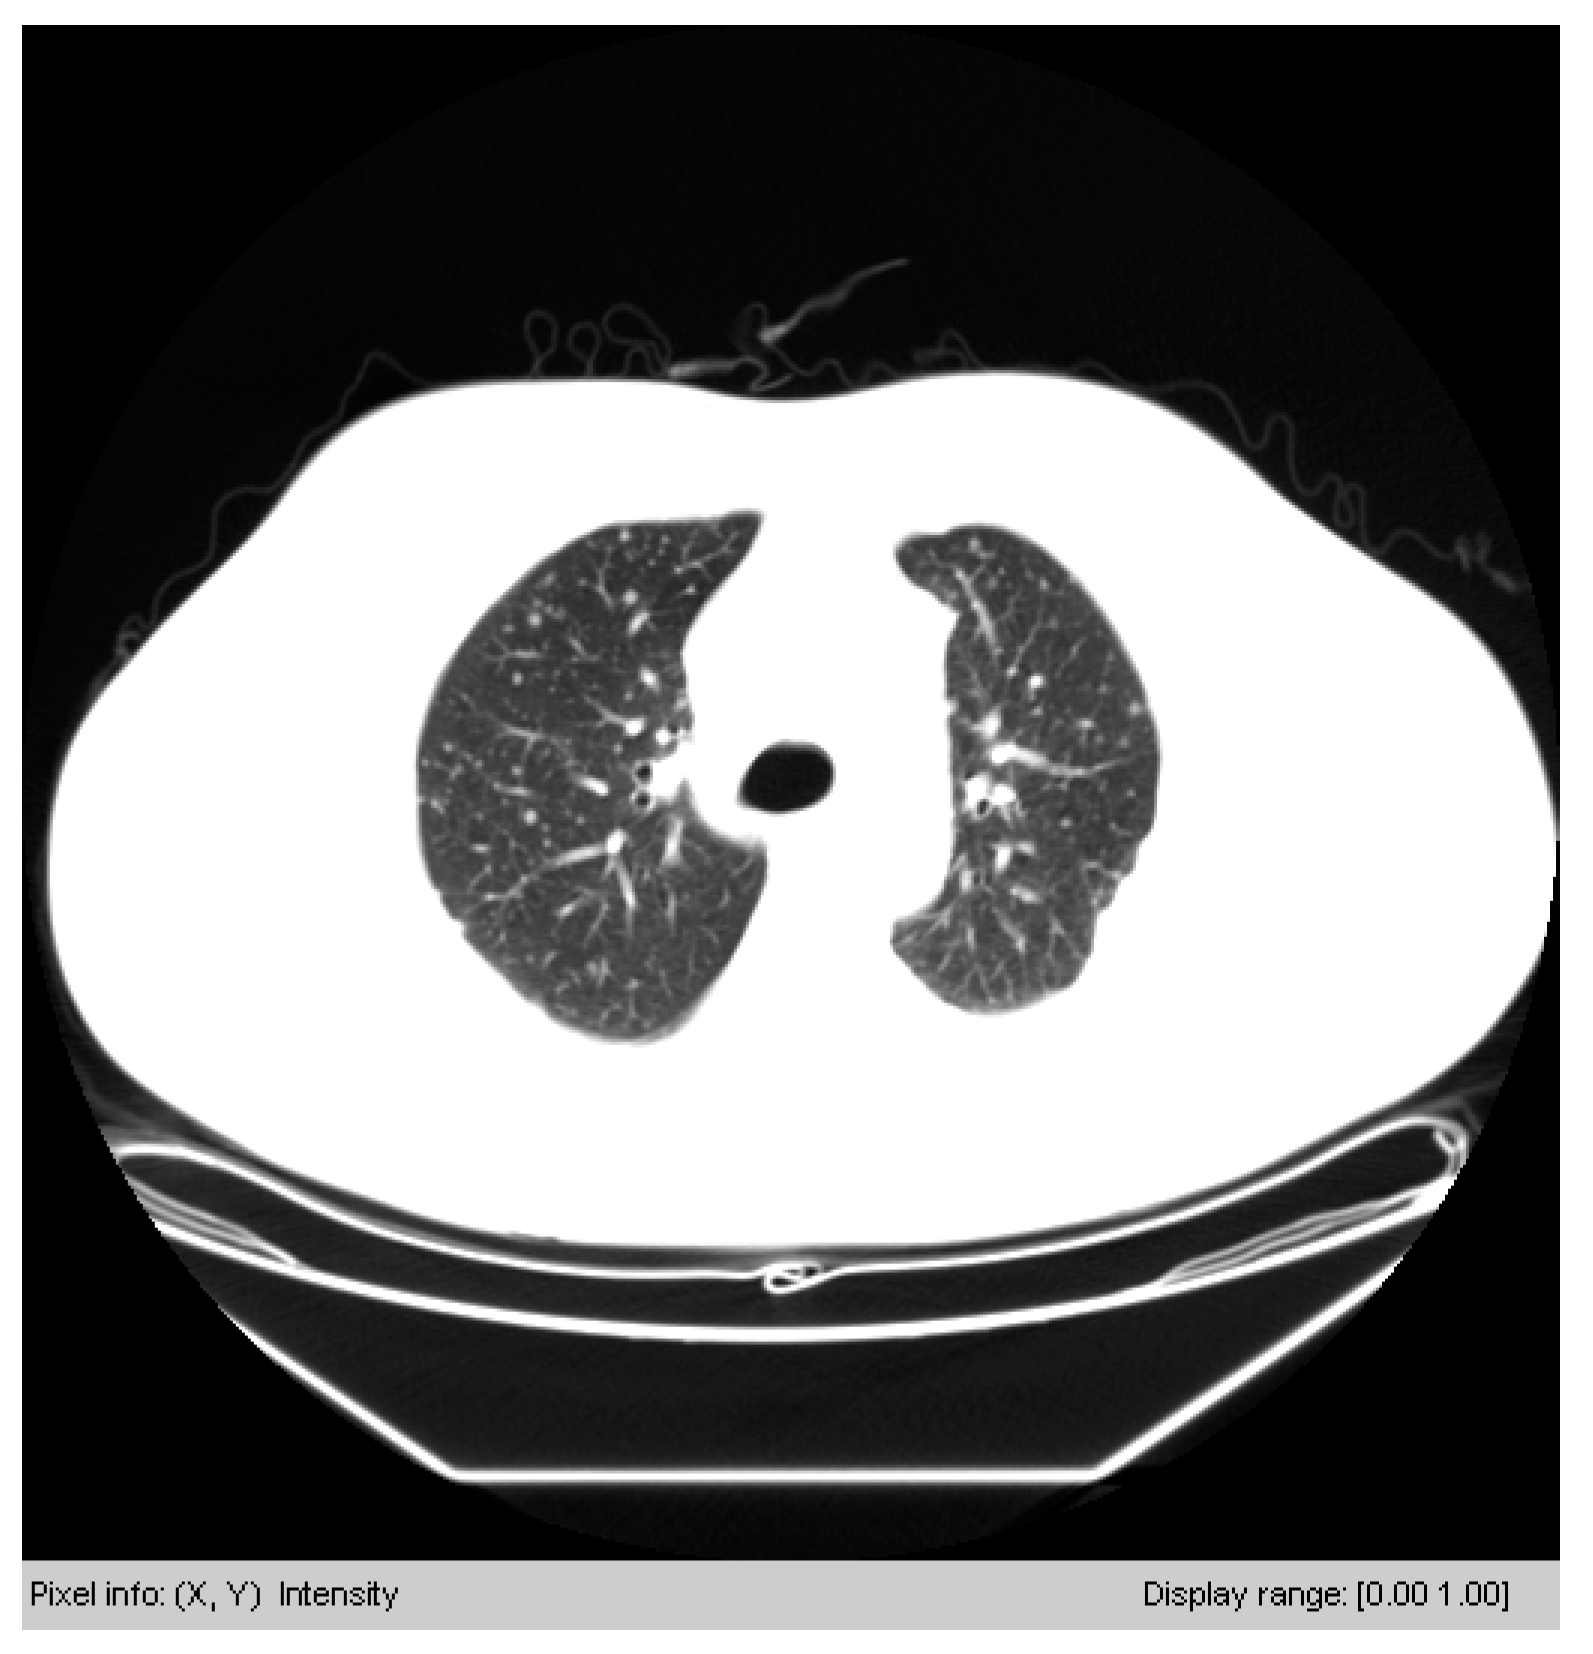

3.3.1. Segmenting the Chest CT Image

| Algorithm 1: Segmenting chest CT image |

| Input: image I (size of I is 512 × 512) begin for i ⃪ 1 to 512 do if > x = i break end end for j ⃪ 1 to 512 do if > y = j break end end for i ⃪ 512 to 1 do if > W = i break end end for j ⃪ 512 to 1 do if > H = j break end end end Output: image I crop from I, width is W-x, and height is H-y |